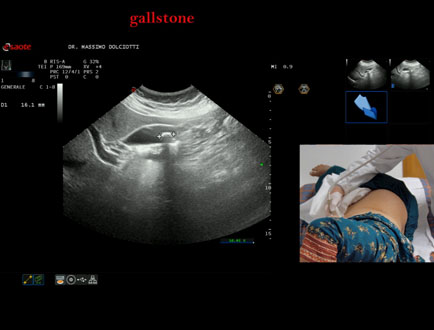

Data inserimento: 13/10/2025

Ecografia del: 07/10/2025

Strumento: Esaote MyLab Eight

Sonda: Convex Multifrequenza 1-8 MHz

Età Paziente: F 49 anni

Motivazione dell'esame: follow up per litiasi della colecisti dopo trattamento con acido ursodesossicolico.

Commento all'esame: le immagini ed il video documentano nel lume della colecisti, immagine iperecogena, delle dimensioni di 16,1 mm, con cono d'ombra posteriore, mobile al decubito, da ricondurre a litiasi.

Conclusioni: litiasi della colecisti (gallstone).

Presentazione: Dr. Massimo Dolciotti - Ancona

Elaborazione digitale: Andrea Dini - Ancona